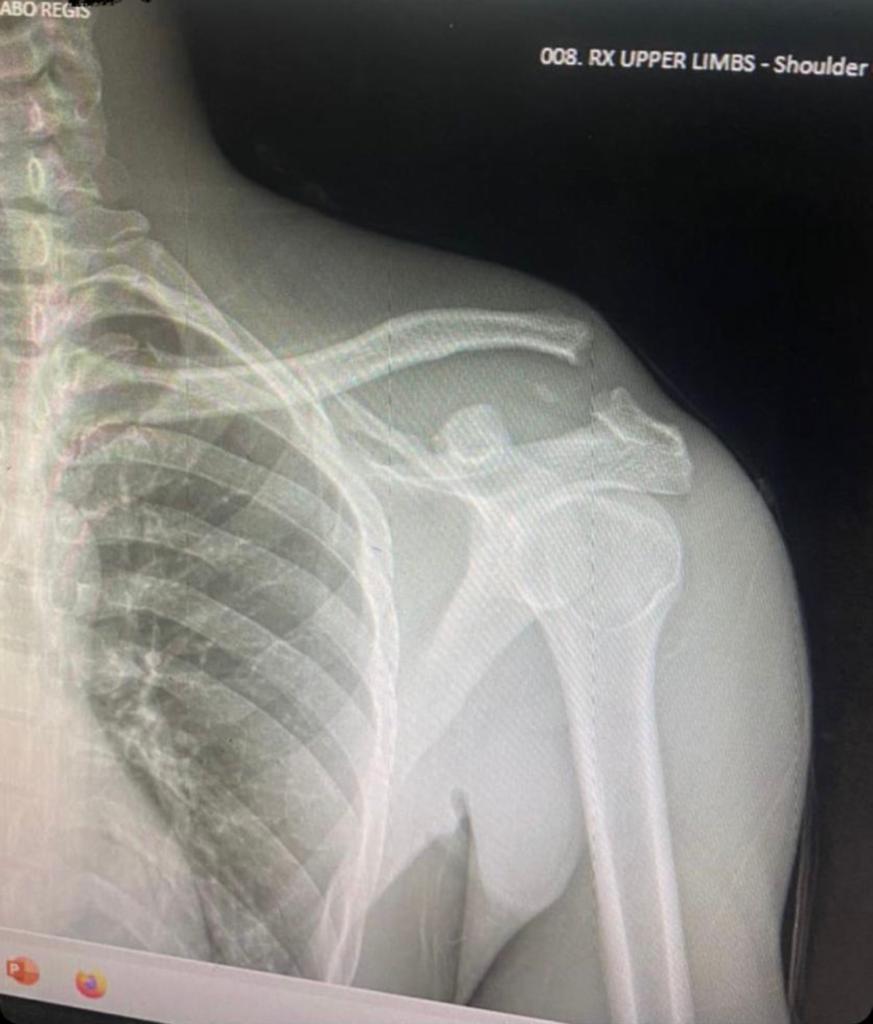

Kuwa Gatanu ubwo Kiyovu Sports yakiraga Etoile de l’Est, hagati mu mukino myugariro wa Kiyovu SC, Mbonyingabo yagize ikibazo cy’imvune agwira urutugu.

Imashini igaragaza ko igufwa rihuza impande ryacitse.

Biteganyijwe ko Mbonyingabo agomba kubagwa.